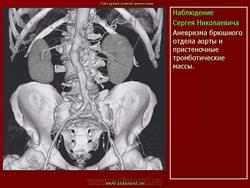

Аневризмы брюшной аорты

Женщина 77 лет. Жалобы на боли в животе. Пальпируется образование в околопупочной области живота. Аневризмы брюшной аорты и обеих общих подвздошных артерий.